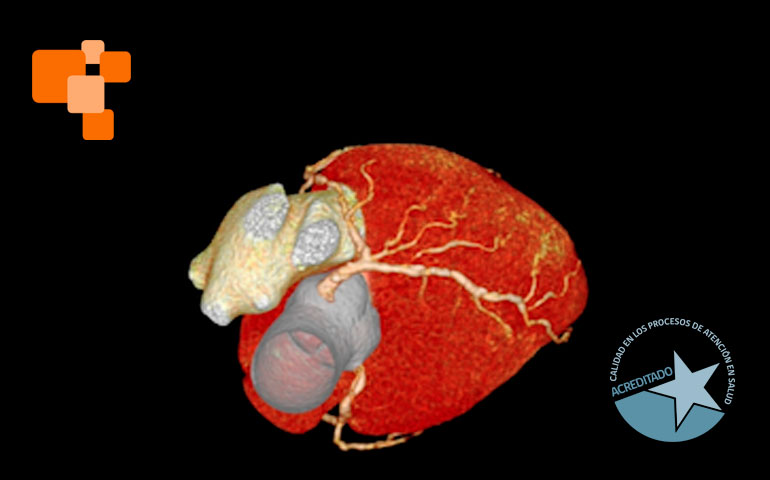

El TAC de calcio coronario es un examen de alta complejidad, realizado usualmente en centros de imagenología avanzada, mide el calcio en las arterias coronarias para evaluar el riesgo de eventos cardíacos futuros. Al proporcionar un score de calcio coronario, permite a los médicos identificar la acumulación de calcio y ajustar tratamientos para prevenir la aterosclerosis, una causa principal de ataques cardíacos. Según expertos, médicos especialistas en cardiologías lo sugieren principalmente para aquellos en riesgo moderado, pacientes que no han tenido síntomas, pero poseen factores de riesgo como hipertensión o colesterol alto.

La tomografía computada para el cálculo del score de calcio coronario permite identificar y cuantificar calcificaciones antes de que se manifiesten síntomas de enfermedad cardíaca, facilitando intervenciones tempranas. Es una técnica de diagnóstico por imagen que, a diferencia de otros métodos más invasivos, ofrece una evaluación rápida y no invasiva de las coronarias.